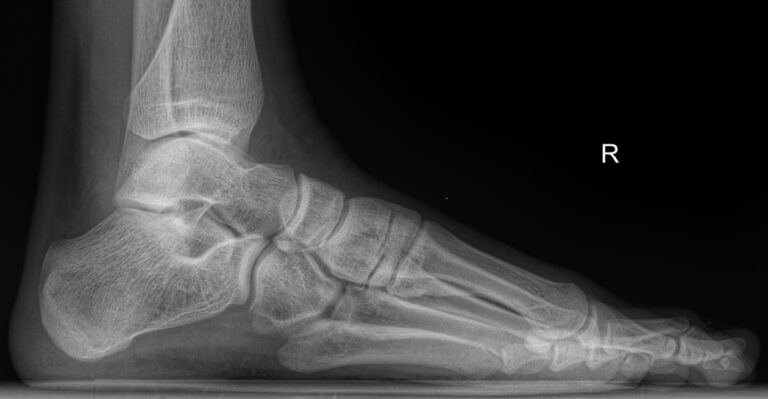

В качестве диагностической процедуры для выявления плоскостопия часто используют рентген. Прицельное исследование стопы позволяет увидеть изменения в ее строении, а также вычислить угол и высоту свода стопы, показатели которых используются для установления стадии болезни.

Что покажет рентген стопы на продольное плоскостопие

На снимке будут отчетливо видны:

• Кости предплюсны;

• Наложенные друг на друга кости плюсны;

• Травмы, в том числе застарелые;

• Патологические изменения видимых суставов;

• Опухоли.

Рассчитывается высота и угол свода стопы и соответствующая им степень плоскостопия.

Никакой подготовки не требуется. Пациент оголяет ногу ниже колена и ставит ее на пластину детектора. При этом вес тела переносится на исследуемую ногу. Жизненно важные органы закрываются защитным фартуком. Съемка выполняется в боковой проекции и идет 1-2 секунды, во время которых важно не шевелиться.